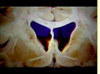

Label the arteries that supply A-C [3]

A = anterior cerebral artery (upper

and medial parts of the cortex)

(orange)

B = middle cerebral artery (lateral

areas of the frontal, parietal, and

temporal lobes) (white)

C = posterior cerebral artery (occipital

lobe and inferior parts of the

temporal lobe) (blue)